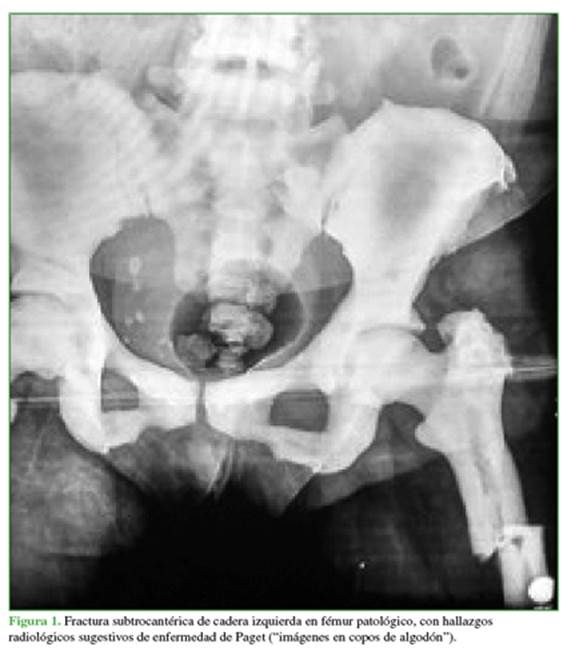

Mujer de 63 años, residente en la ciudad de Medellín, Colombia. Se trataba de una trabajadora independiente con diagnóstico previo de enfermedad de Paget de presentación poliostótica e historia familiar de enfermedad de Paget, diagnosticada de forma incidental por los hallazgos radiológicos y el antecedente familiar. En 2015, la paciente sufre una caída desde su propia altura y se comprueba fractura subtrocantérica de cadera izquierda, a la cual se le dio manejo quirúrgico en otra institución. Se considera que la fractura se presentó en hueso previamente patológico y comprometido por la enfermedad de Paget (Figuras 1 y 2).

Los hallazgos radiológicos incluyen, en la primera fase, áreas bien delimitadas de osteolisis; en la segunda fase, la aparición de áreas en “copos de algodón”, lo que indica la actividad ósea mixta, y, en la tercera fase, dejan de ser predominantes las imágenes líticas, para pasar a ser predominante el hueso con características esclerosas. Aunque las radiografías representan una gran ayuda para el diagnóstico, la mejor ayuda diagnóstica para identificar la presentación poliostótica es la gammagrafía ósea.12